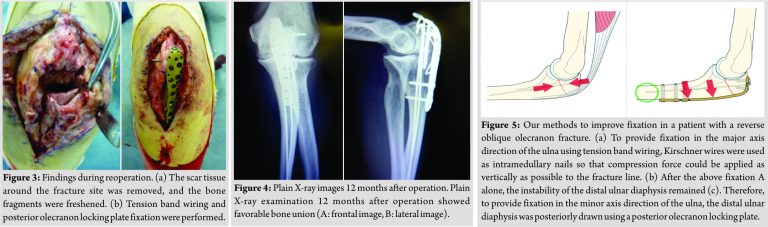

Reoperation was performed. The broken wire and scar tissue at the fracture site was removed, and the bone fragments were freshened (Fig. 3a). Subsequently, TBW was performed using K-wires as intramedullary nails so that compression force could be applied as vertically as possible to the bone fragments. Furthermore, for further control of distal bone fragment instability, olecranon locking plate fixation (VA-LCP olecranon plate, Depuy Synthes, Tokyo, Japan) was performed using a posterior approach (Fig. 3b). At present, 12 months after the operation, the range of elbow motion is 130 for flexion, -10 for an extension, 85 for pronation, and 85 for supination. The visual analog scale score was 2/10, Quick Disabilities of the Arm, Shoulder, and Hand score were 2.27/100, and the Mayo Elbow Performance score was 85/100 (Good). Plain X-ray examination showed favorable bone union (Fig. 4a and b).

Concerning surgical treatment for general olecranon fractures, Tarallo et al. reported a high rate (45%) of post-operative complications (such as wire loosening, skin disorder, infection, and non-union) describing that TBW is not a straightforward technique [4]. Therefore, there was a recent study recommending the active use of olecranon locking plates [5]. There have been the following opinions about surgical treatment for reverse oblique olecranon fractures as was observed in this patient. Iga et al. reported that there is anterior instability of the distal bone fragment/ulnar diaphysis in reverse oblique olecranon fractures, and TBW alone is inadequate to control this instability [6]. In addition, concerning whether K-wires should be used as intramedullary nails or transcortically placed through the anterior cortex, van der Linden et al. reported that K-wire instability developed in 75% of cases treated with intramedullary K-wires, and significantly favorable fixation could be obtained in cases treated with transcortical K-wires penetrating the anterior cortex [7]. Therefore, in patients such as our patient with reverse oblique fractures, we considered that methods to achieve two directional favorable fixation (in the major and minor axis directions of the ulna) are necessary. Favorable fixation in the major axis direction of the ulna can be achieved using TBW. As a method to apply compression force as vertical as possible to the bone fragments, K-wires were used as intramedullary nails (Fig. 5a). Favorable fixation obtained using TBW could be confirmed during the operation, but the instability of the distal ulnar diaphysis remained as van der Linden et al. reported [7]. To overcome the anterior instability of the ulnar diaphysis, which could not be controlled using K-wire intramedullary nails, the bone fragments of the diaphysis were posteriorly drawn using a posterior olecranon plate, and fixation in the ulnar minor axis direction was obtained (Figs. 3b, 4b, and 5b). When olecranon plates, mainly locking plates, are used, attention should be paid to the possible development of complications such as skin disorders [8]. Some authors have the opinion that low profile plates instead of locking plates should be used [9]. In our case, a locking plate was used, which is a limitation of our technique. Informed consent should be obtained from patients after an adequate explanation of the possible complications. When complications develop, coping including removal of intramedullary nails is necessary. Despite these disadvantages of olecranon locking plates, the combination of TBW and plates should be actively considered in reverse oblique olecranon fractures for which adequate fixation cannot be provided by TBW alone.